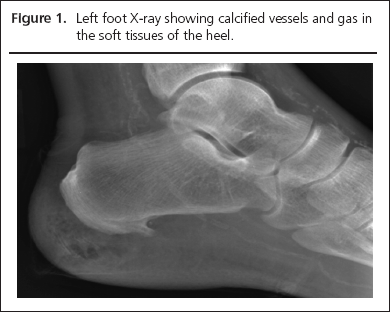

Left foot X-ray revealed gas in the soft tissue of the heel and calcified vessels (Figure 1). He was commenced on broad-spectrum antibiotics according to the trust’s guidelines for diabetic foot infection.

15-0051-Herring-aop-figure1